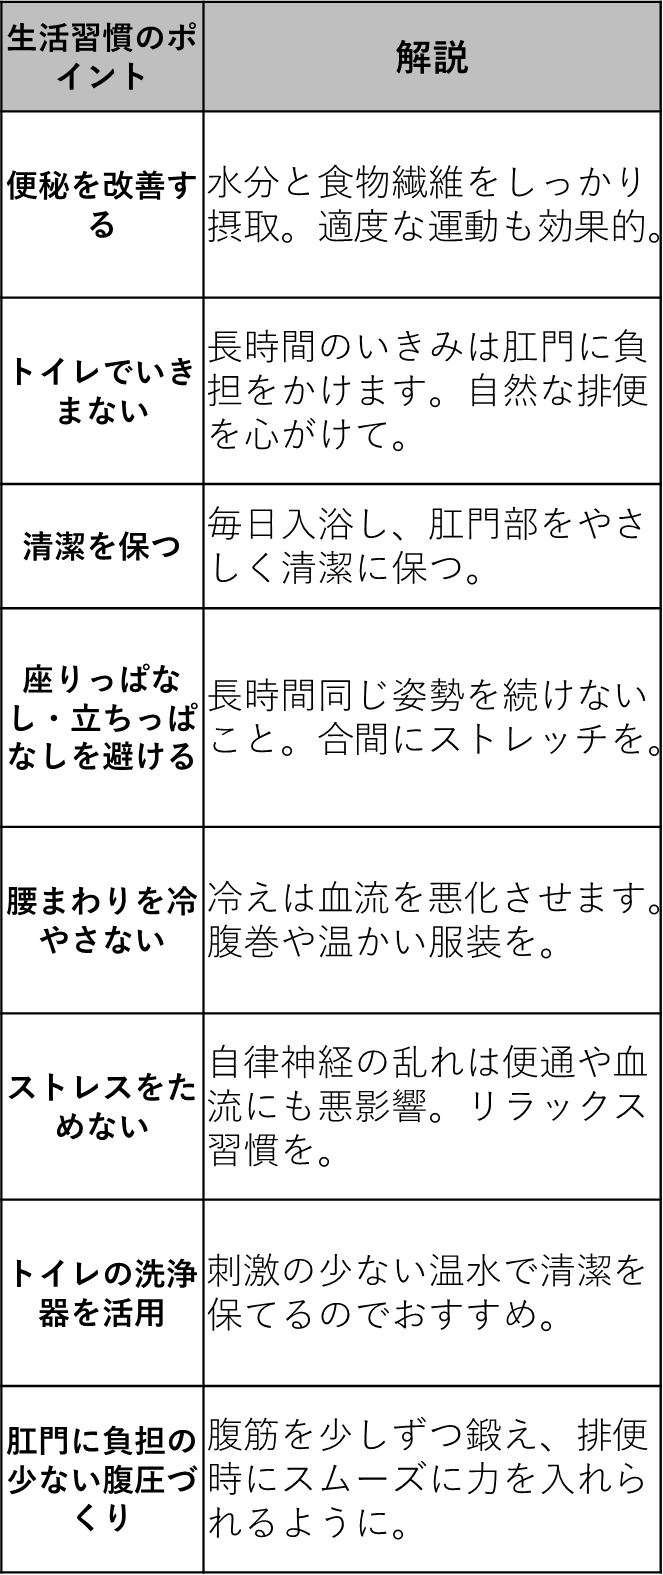

痔に効くツボこうさい (208 無料写真)

痔」の改善に効果的なツボの位置ファイテン株式会社 phiten。

痔」の改善に効果的なツボの位置ファイテン株式会社 phiten。

痔に効くツボ 見つけ方と押し方を紹介 肛門周辺の血流を改善するツボと足裏ゾーン特選街web。

痔」の改善に効果的なツボの位置ファイテン株式会社 phiten。

痔」の改善に効果的なツボの位置ファイテン株式会社 phiten。

痔に効くツボ 見つけ方と押し方を紹介 肛門周辺の血流を改善するツボと足裏ゾーン特選街web。